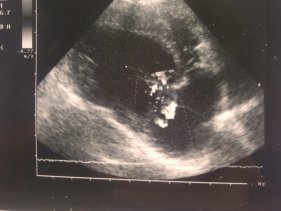

La cardiologia si occupa delle patologie del sistema cardio-circolatorio. La funzione del cuore è molto complessa (p.es. ritmo, funzione di pompaggio, pressione). La diagnosi, grazie ai più moderni ausili, è solitamente facilmente attuabile e molto veloce. Utilizziamo allo scopo, oltre alle analisi cliniche, moderne attrezzature diagnostiche quali elettrocardiografia (ECG), apparecchio radiologico Röntgen e moderni metodi di ecografia (compresa la classica ecografia Doppler).